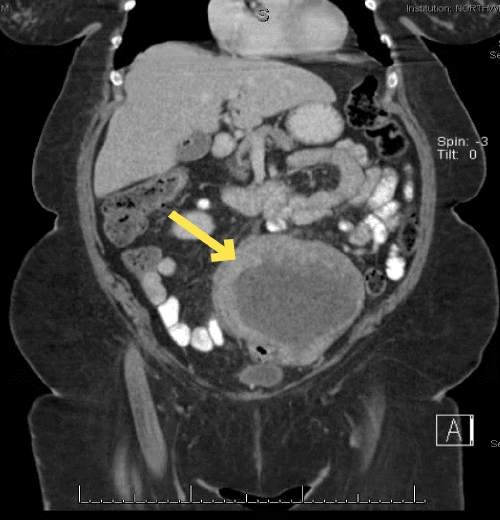

B) Necrotic mass demonstrating adherence to the colon (yellow arrow)

The patient underwent radical resection of the mass. Intraoperatively, the mass was found to be significantly adhered to the sigmoid and descending colon, requiring en bloc resection of the sigmoid colon (Figure 1B). The patient recovered well postoperatively; she did require a postoperative transfusion of one unit of packed red blood cells due to acute blood loss anemia. She was discharged home on postoperative day nine.